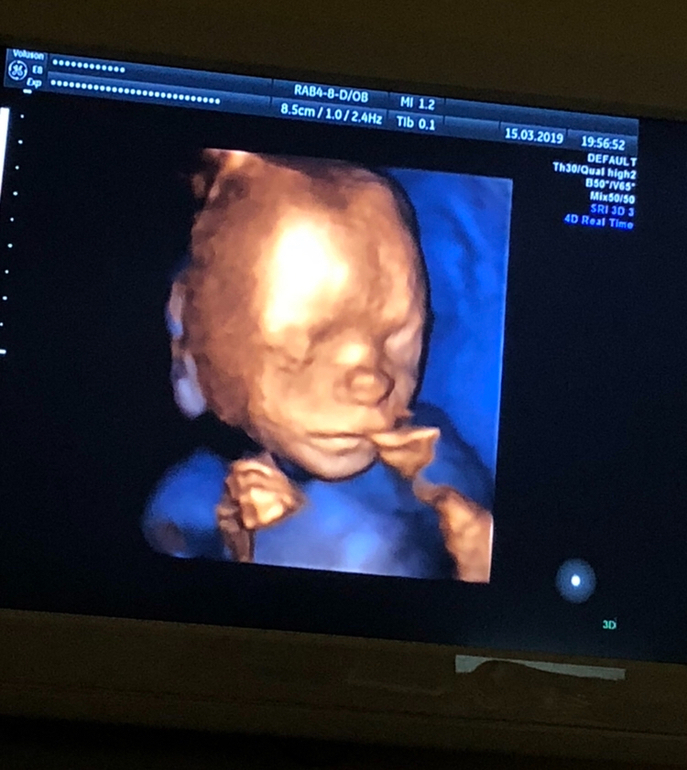

20 недель,2-ой скрининг,фото 3D

Результаты: УЗИ, КТГ, доплера, скринингаВчера было ровно 20 недель,2 скрининг,посмотрела как он вырос,такой хорошенький,палец сосал)) весит 350 гр. Все у него хорошо ттт. Хоть тут многие и говорили,что в 13 недель это рано для определения пола,но я считаю что нет,все зависит от врача,вчера специально даже спросила ее ошибалась ли она на сроке 13 недель с полом(первого,второго и этого третьего езжу только к ней скрининги делать), сказала,что с 13 недель она ни разу не ошибалась,что с такого срока уже все понятно. Вчера только подтвердила,что это ещё один мальчик😂. В спб она одна из лучших узи специалистов и кто скрининги делает идеально. Вдруг кому понадобится фамилия ее Лисина,работает в роддоме на фурштатской. Малыш вчера идеально лежал,шевелился во всю,показывая себя во всей красе и во всех ракурсах,видимо хотел угодить отцу,который тоже приехал посмотреть)) И фото мне на память,на ББ всегда проще зайти и посмотреть фото,чем потом искать их дома)) 😄😄